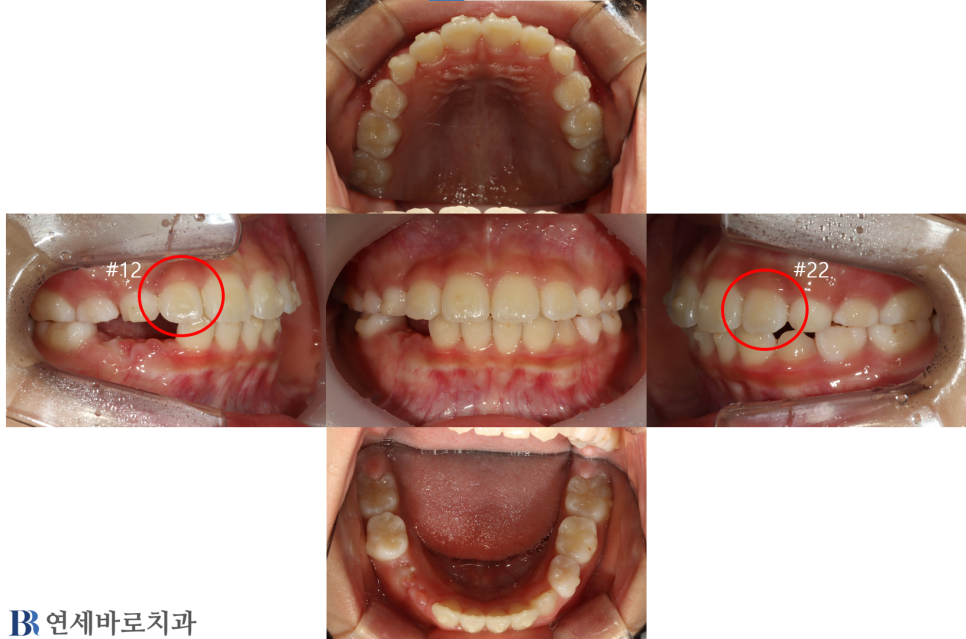

치아교정

소아 교정 치료 #6